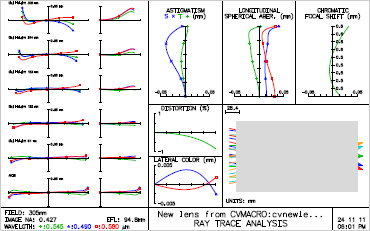

- Ray fan